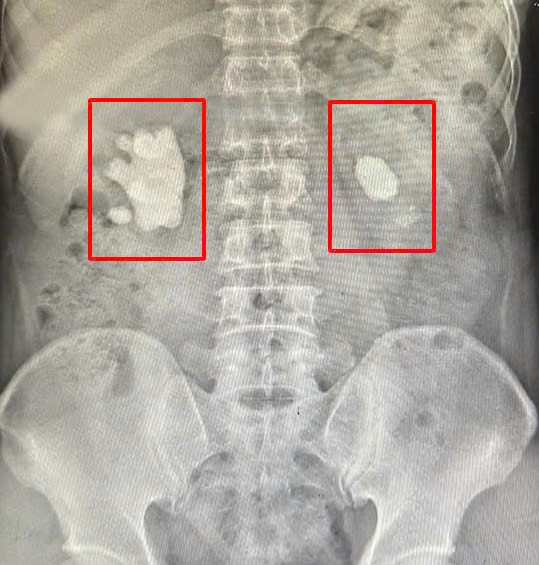

Calculs coralliens sur les deux reins, visibles sur la radiographie d'un patient à Quang Ninh

Les calculs coralliens sont des calculs ramifiés qui remplissent tout ou partie du bassinet et des calices rénaux. Ils sont généralement composés de struvite (phosphate d'ammonium et de magnésium) ou d'apatite (carbonate de calcium). On les appelle souvent « calculs infectieux » car ils sont étroitement liés aux infections urinaires causées par des bactéries capables de décomposer l'urée en ammonium. La particularité des calculs coralliens est qu'ils se logent exclusivement dans les calices du bassinet et n'apparaissent pas ailleurs, par exemple dans la vessie ou l'uretère. Sur les radiographies, leur aspect rappelle celui des bois d'un cerf.